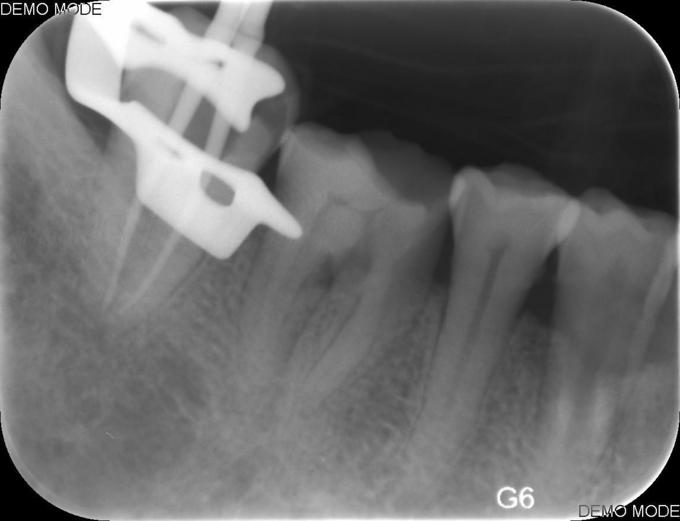

诊断:牙髓坏死 治疗#47碧兰麻下开髓,封三甲+OC球,ZOE暂封,嘱2周后复诊,不适随诊。 去暂封,清理髓腔及根管,双氧水和生理盐水交替冲洗,测WL,拍片试尖达工作长度,根管内导入糊剂,侧压充填中下段,热牙胶充填上段,X线示恰填,树脂充填修复。